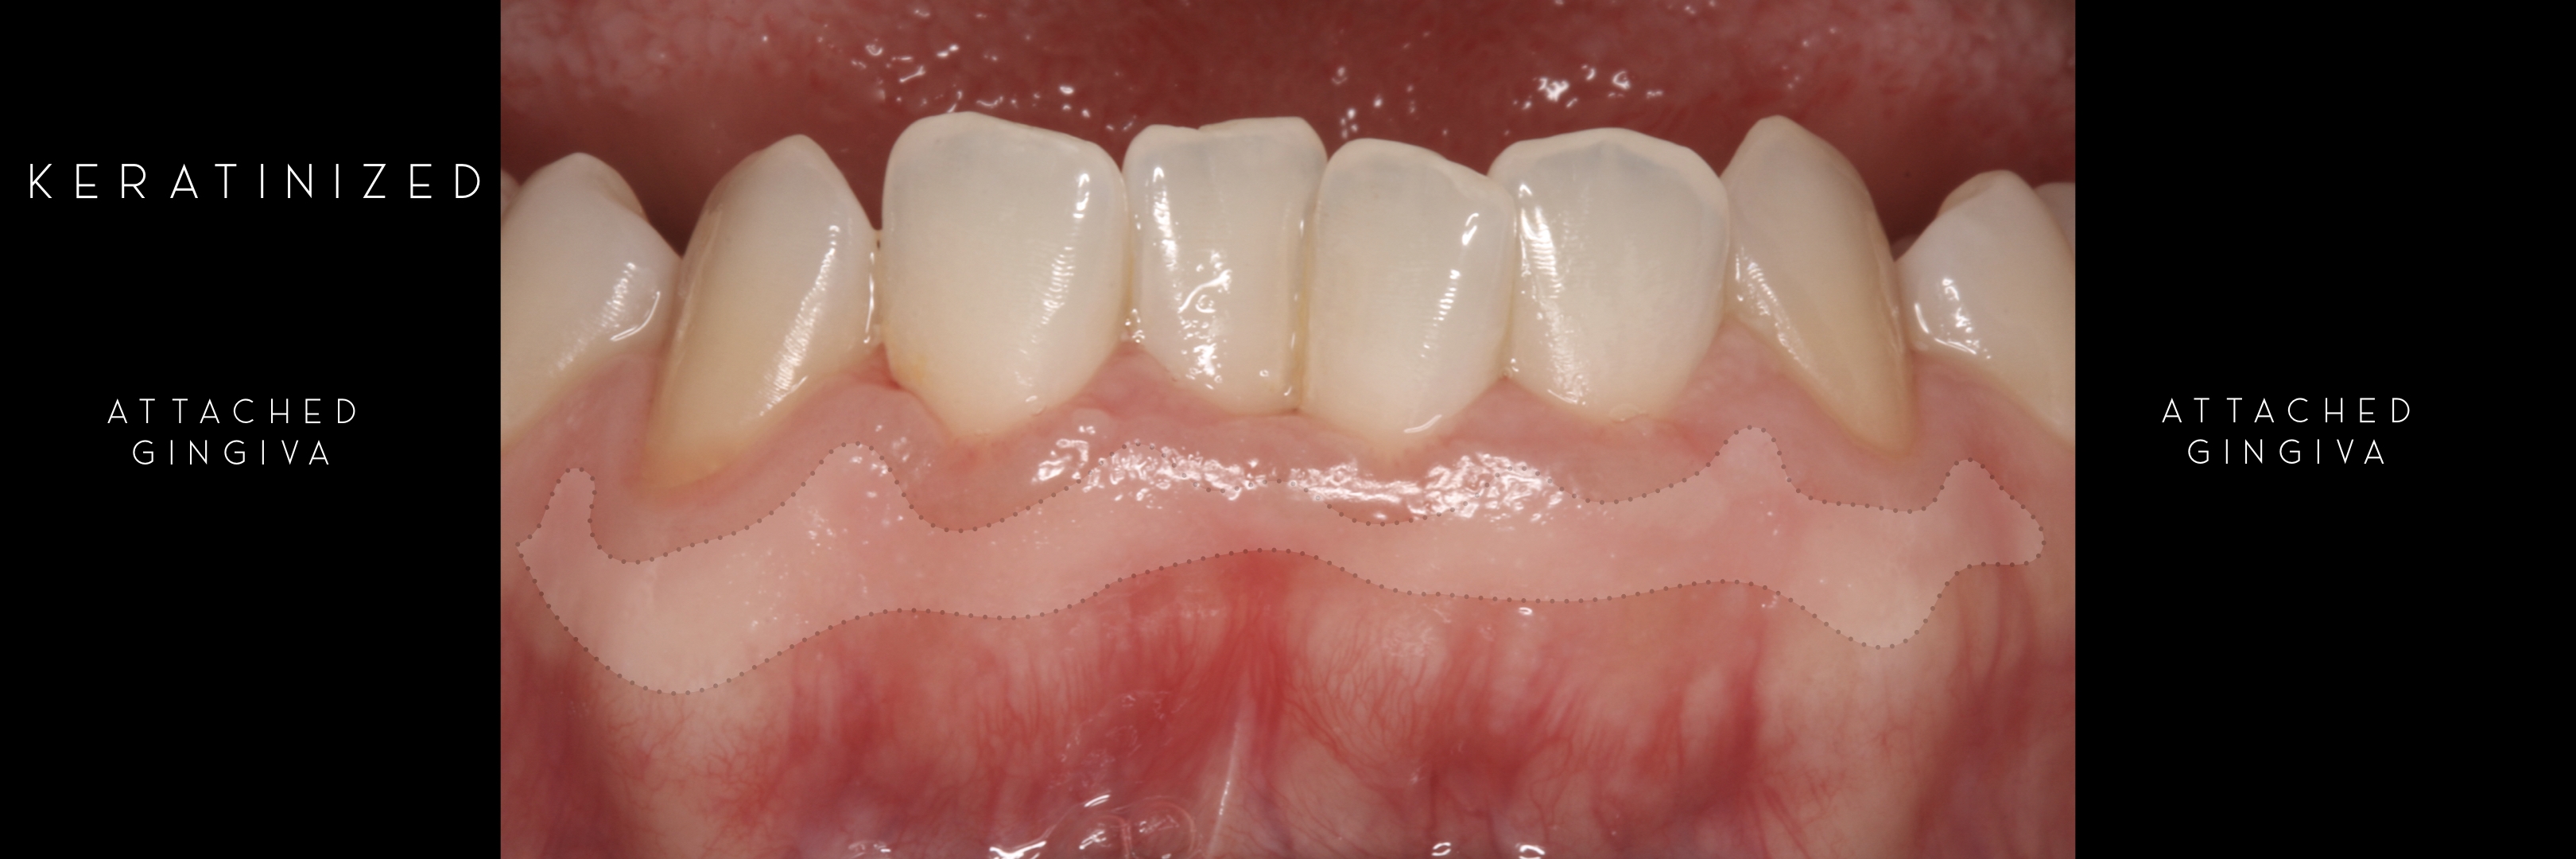

KERATINIZED gingiva includes

the free gingiva

(marginal gingiva & papillae)

and the attached gingiva extending from the gingival mar­gin to the mucogingival junction.

Generally we tend to forget about these 2 parameters, free and the attached gingiva are both essential parts of the keratinized gingiva.

This meaning that keratinized (load bearing capacity) is a mechanical characteristic that makes up for attached gingiva, providing it's immobility,  but also is of such importance as the thickness it provides around whatever perforates the epithelium, be it implants or teeth, being also keratinized (having load bearing capacity) at this location.